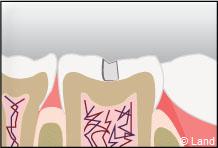

Un inlay reconstitue l’anatomie dentaire en comblant une cavité taillée dans la dent.

Inconvénient mineur : sauf dans certains cabinets équipés en CFAO (Conception et Fabrication Assistées par Ordinateur), cette technique nécessite 2 séances de soins, car une étape de laboratoire s’intercale entre la réalisation de la cavité et la pose et le scellement des inlays onlays réalisés en métal, en résine composite ou en céramique.